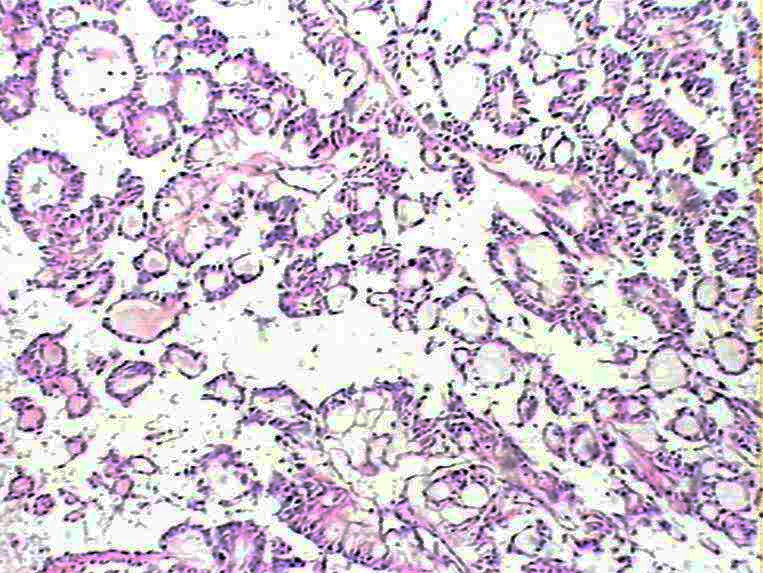

女48 骶尾部皮下见一结节状肿物,,9*6*4cm,切面实性,分叶状,灰白灰红灰黄色,质软。

• 骶尾部肿瘤图1

• 骶尾部肿瘤图2

• 骶尾部肿瘤图3

• 骶尾部肿瘤图4

• 骶尾部肿瘤图5

粘液性室管膜瘤

粘液乳头状室管膜瘤,

是粘液乳头状室管膜瘤,但是楼主提供相关病史、临床资料不能少

会诊粘液乳头状室管膜瘤

骶尾部可以有原发的室管膜瘤,并不一定是转移的

这种患者可能为神经管残留皮下或有脊柱裂等情况

HE切片质量有待提高,但是这个部位,这种乳头状机构,诊断粘液样乳头状室管膜瘤没有问题。